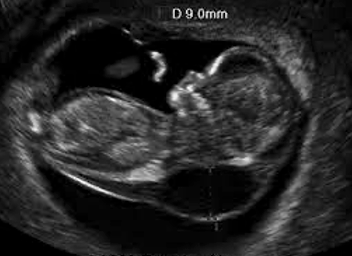

What is this condition?

Cystic hygroma

Also accepted: Thickened nuchal translucency